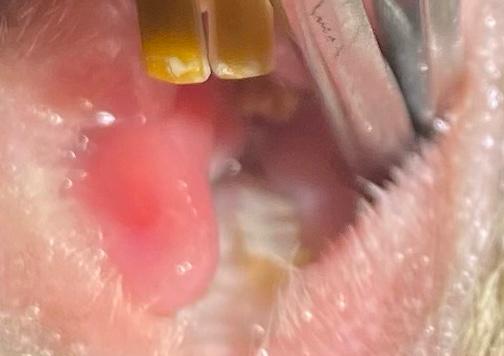

Добрый день. По началу все казалось, что будет хуже и хуже. На третий день дегу кормился только со шприца, ничего другого есть не мог. Заметили, что резцы начали отрастать и стачиваться неровно.

Изображение

Дальше хуже

Подсказали, что возможны проблемы с задними зубками. Начали давать обезбаливающее (мелоксикам). Записались к ветеринару. Резцы подточили, с задними зубами все было в порядке

Предположили, что проблема с челюстью, возможно, вывих

Хотелось надеяться на лучшее. Зубки после визита.

После визита к ветеринару дегу спал до вечера, вечером уже пытался грызть гранулы, что пока не получалось, но слегка вымоченые гранулы уже кусал. На второй день уже пытался грызть камень. Через пару дней заметили, что резцы снова начали стачиваться неправильно.

Продолжили обезбаливающее, в надежде на то, что был просто ушиб челюсти. Через некоторое время резцы стали выравниваться.

Зубки на сегодняшний день такие.

В общем, все обошлось несколькими неделями переживаний. Дегу хотя и похудел немного, весьма активен и весел.